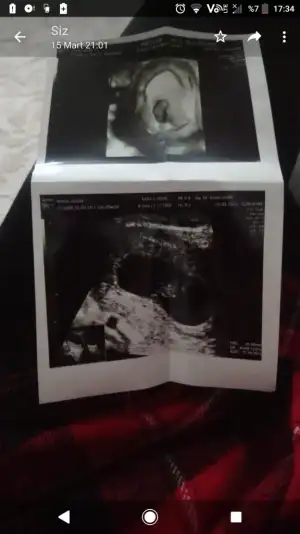

Evet sadece ihtimal ben yaptirmadim bile ikili testAceleci davranıp sadece kan sonuçlarına bakarak bir an telasa kapıldım sonra hastanenin sayfasından asıl sonuca ulaştım ve grafikli vs cok şükür risk cok çok düşük olarak anladım ben. Kendi doktoruma yolladım bakalim o ne dicek. İkili test sadece ihtimal veriyor sonucu takmicam hic diyodum ama öyle olmuyomus

Ultrasonla ense kalinligi falan olcuyolar o yuzden demistirKızlar hiç bilgim yok size danışmak istedim.

Doktor ikili test yaptırdıktan hemen sonra bana da randevu al gel dedi. Rutin muayene olarak mi çağırdı bilmiyorum. Test sonrası böyle erken cagiriyolar mi? Testten Yarim saat 45 dk sonra bana gel dedi.

Kesede ufak bir bozukluk varmış o yüzden midir, son kontrolde gayet olumlu konuşmuştu